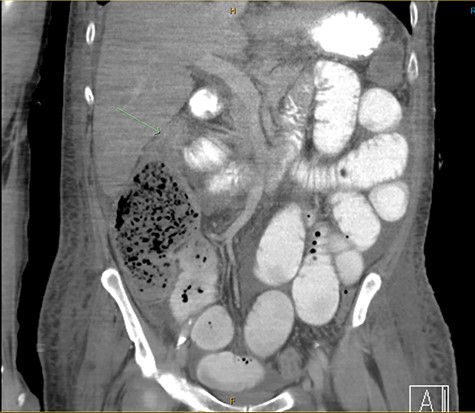

Subsequently, he remained stable in his systemic inflammatory state tachycardic to 115, blood pressure of 114/59 with minimal noradrenaline requirement, and febrile to 39°C. He had continued small liquid stools and developed larger nasogastric aspirates. Abdomen was tense, distended and tender on the right lower quadrant. He was not peritonitic and bowel sounds were not appreciable. Repeat imaging demonstrated a thickened caecal wall, pericaecal fat stranding and a transition point in the ascending colon secondary suspected stercolith (Fig. 1).

CT demonstrated a thickened caecal wall with pericaecal fat stranding; gastrografin had only passed through small bowel with a transition point identified in his ascending colon secondary to a suspected stercolith.